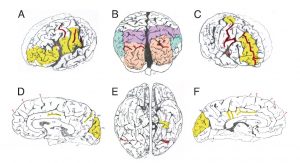

نتایج اولیه تحقیقات روی مغز این فیزیکدان برجسته چندان جالب از آب در نیامد، چون مغز اینشتین حتی از متوسط ابعاد انسانهای دیگر هم کوچکتر بود و بر اثر افزایش سن دچار زوال شده بود. اما بعدتر در سال ۱۹۸۵ معلوم شد در دو بخش مغز او نسبت سلولهای غیر عصبی به ازای هر نورون ( سلول عصبی ) به طرز عجیبی بیشتر از بقیه افراد است. هاروی در سال ۱۹۹۰ کشف کرد قسمت بالایی وسط نیمکره مغز اینشتین که لوب یا لخته آهیانه نامیده می شود، فاقد یک ساختار شیار مانند رایج در مغز انسانهای دیگر است. محققان می گویند احتمالا این فقدان باعث شده اتصالات عصبی که وظیفه درک فضایی و محاسبات را بر عهده دارند، بیشتر شوند.

به تازگی دین فالک، انسان شناس دانشگاه ایالتی اوهایو و همکارانش ۱۲ عدد از عکسهای هاروی را از موزه ملی سلامت در ایالا متحده قرض گرفته و آنها را با تصاویر مشابه از ۸۵ نمونه مغز دیگر مقایسه کرده اند. در این تحقیق ساختارهایی مشخص شدند که در تحقیقهای قبلی نادیده مانده بود. مثلا توسعه بیش از حد قشر حسی نیمکره راست مغز احتمالا باعث شده بود اینشتین ویولن نواز خوبی از آب در بیاید. پیچیدگی ها و الگوهای چین ها در نقاط خاصی از مغز اینشتین مثل قشر جلویی پیشانی، لوب آهیانه و قشر بینایی متفاوت است. ساختار چین ها در قشر پیشانی که برای تفکر انتزاعی از جنس افکاری شبیه نظریه نسبیت کافی در اختیار مغز به کار می رود، بسیار پیچیده است و احتمالا این پیچیدگی فضا و ساختار عصبی کافی در اختیار مغز او قرار داده تا بتواند به طرز غیر متعارفی فکر کند.